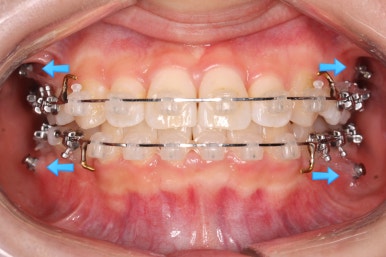

연산동교정치과에서 이번에 진행한 방법은 비발치교정이기 때문에 미니스크류를 잇몸뼈에 식립합니다.

위 사진에서 화살표 부분이 미니스크류인데요.

어금니쪽 잇몸에 아주 작은 나사가 보이실텐데요. 이것을 이용해서 전체 치열을 뒤로 당겨넣습니다. 물론 사랑니는 제거가 된 상태입니다.

아랫니도 어느 정도 많이 가지런해졌습니다.

윗니를 계속 당겨 넣습니다.

만족을 하실 때까지 계속계속 넣고 그리고 입 안에서는 허락하는 만큼 계속 당겨 넣습니다.

이제 아래쪽도 당겨 넣습니다.

원하는 만큼, 허락하는 만큼 계속 당겨 넣습니다. 연산동교정치과에서는 비발치 돌출입 교정을 위해 총 4개의 미니스크류를 식립했습니다.

이제 거의 다 되감을 알 수 있습니다. 앞니의 뻐드러짐도 많이 좋아졌고 전반적으로 들어간 양도 적절해 보입니다.